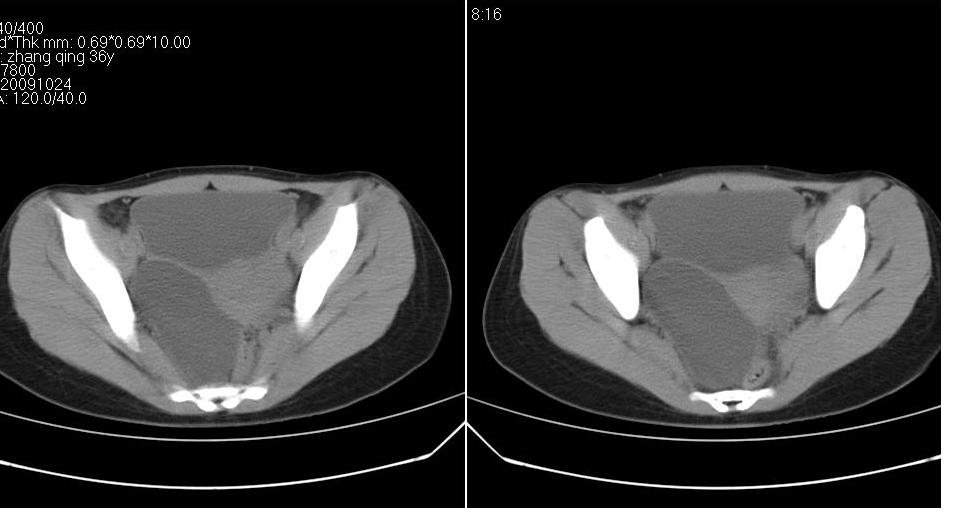

标题: CT22811:女 36岁,B超提示右侧附件囊性占位。 [打印本页]

标题: CT22811:女 36岁,B超提示右侧附件囊性占位。

右侧卵巢囊肿

右侧卵巢囊肿。

支持右侧附件良性囊性占位性改变。

手术结果证实为右侧输卵管囊肿。

输卵管囊肿罕见,从影像上无法同卵巢囊肿区分。

还是报右侧附件区良性囊性占位性改变       至于输尿管或卵巢囊肿不太好鉴别